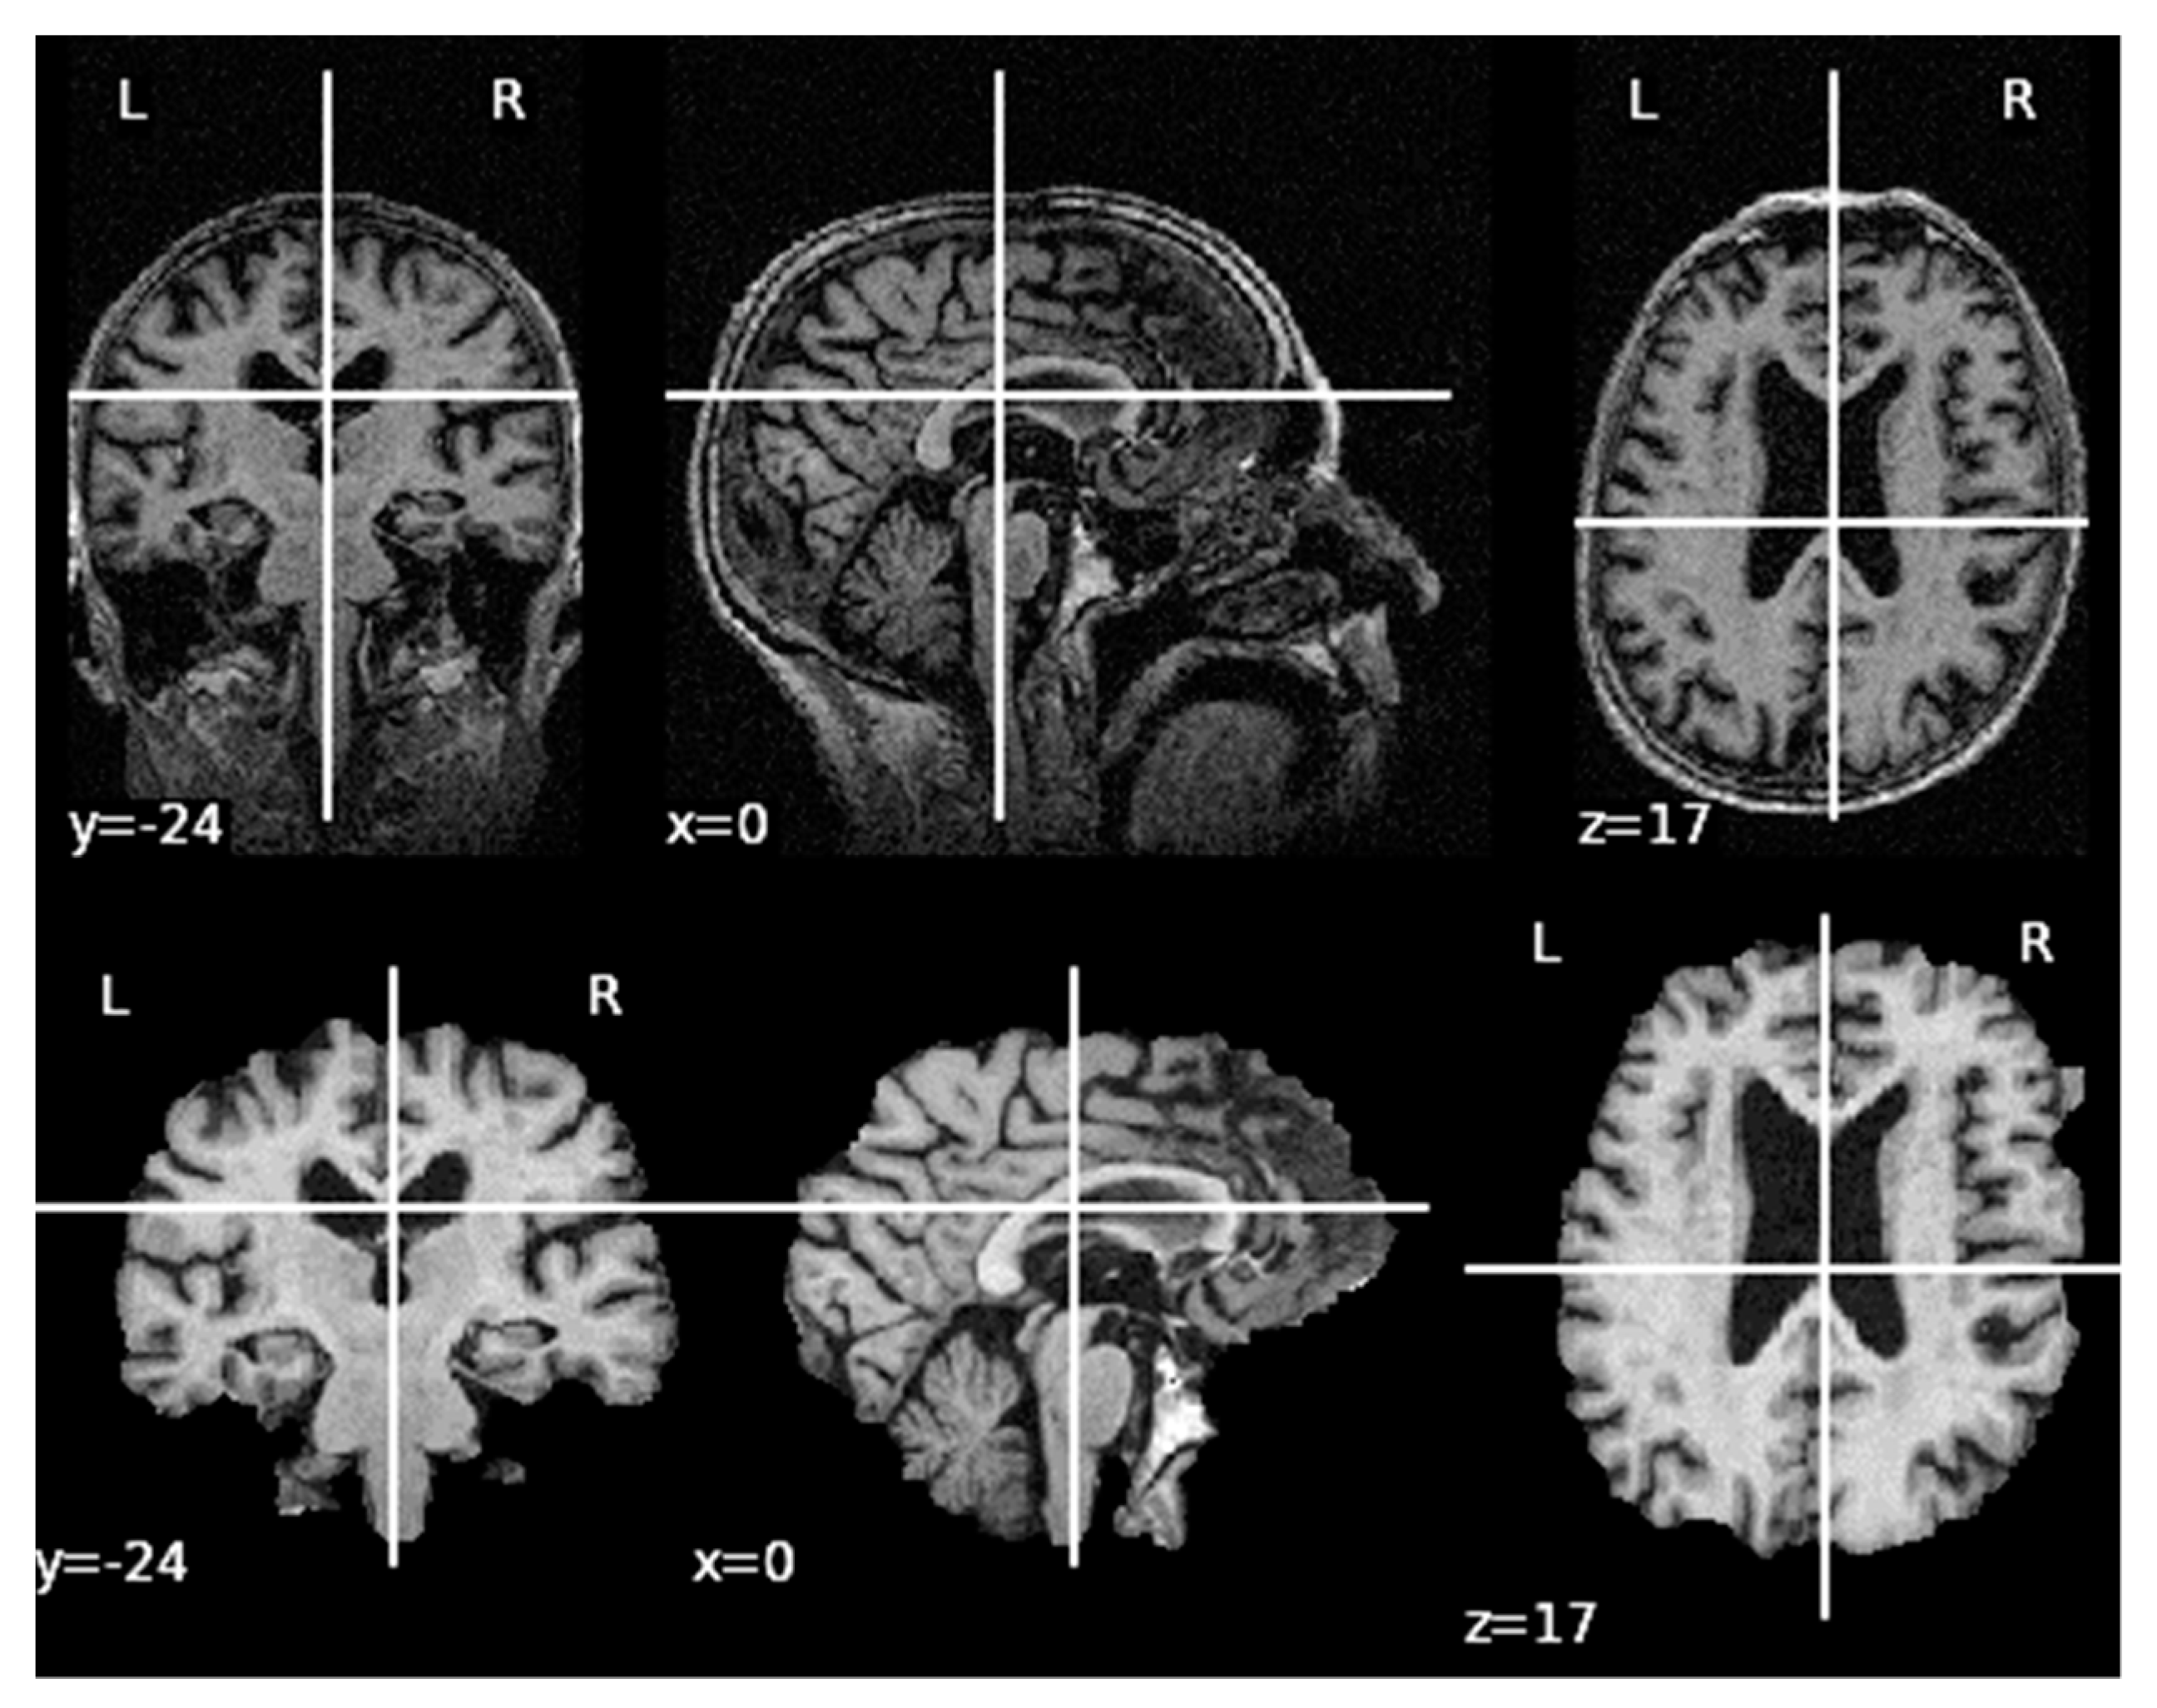

Appendix B. Pre-Processing of Raw MRI Volumes

- Image registration, using the Flirt tool from the AFNI library: all images included in the RAW folder of the OASIS-2 database are registered in pairs.

- Averaging registered images, using the fslmaths tool from the FSL library: all resultant images from the registration process are averaged to obtain one unique image.

- Image resampling, using the 3dRESAMPLE tool from the AFNI library: the resultant averaged image is resampled to obtain 1 × 1 × 1 mm voxels.

- Change volume slice order, using the fslswapdim tool from the FSL library: As original images do not have the same slice anatomical plane view as the pre-processed volumes in OASIS-1 and the aim of the pre-processing part is to replicate as well as possible the pre-processing performed in OASIS-1, the dimension slices of the resampled image are swapped.